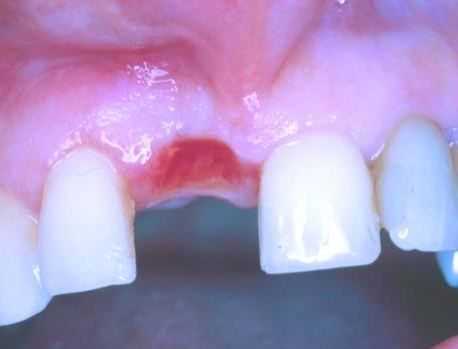

Наиболее распространенным симптомом опухоли полости рта является образование незаживающей язвы на губе, слизистой щеки или на дне ротовой полости. На губе рак может возникнуть на верхней или нижней границе кожи и слизистого покрова ее внутренней поверхности или в примыкающей области, например на губном желобке. При этом опухоль распространяется на всю губу.

Первичная опухоль может возвышаться над поверхностью кожи или слизистой, выглядеть изъязвленной или представлять собой выемку. Она может быть пигментирована, с четкими границами или без них, вызывать болезненные ощущения или не беспокоить больного. Во многих случаях опухоли полости рта обнаруживаются на приеме у стоматолога, причем иногда они развиваются под протезами.

Обычно при осмотре обнаруживается эритематозное изъязвление, возвышающееся над поверхностью кожи или слизистой и часто содержащее некротическую зону. Большие опухоли языка могут снижать его подвижность и влиять на речь.